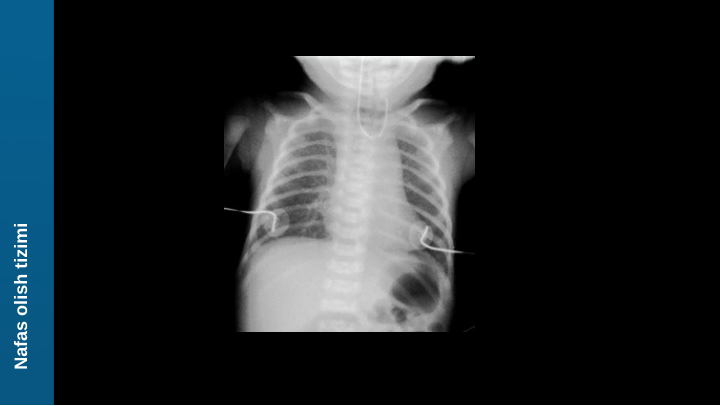

traxeozofagial oqma (TEF) bilan qizilo'ngach atreziyasi (EA) eng

keng tarqalgan (85%) va ko'pincha bachadonda polihidramnioz sifatida

namoyon bo'ladi (homilaning amniotik suyuqlikni yuta olmasligi

sababli).

Yangi tug'ilgan chaqaloqlar birinchi oziqlantirishda oqadi,

bo'g'iladi va qusadi . TEFlar havoning oshqozonga kirishiga imkon

beradi (CXRda ko'rinadi). Siyanoz laringospazmdan 2 ° gacha

(reflyuks bilan bog'liq aspiratsiyani oldini olish uchun). Klinik

tekshiruv: nazogastral naychani oshqozonga o'tkazmaslik .

H - tipidagi fistula H harfiga o'xshaydi . Sof EAda CXR gazsiz

qorinni ko'rsatadi.